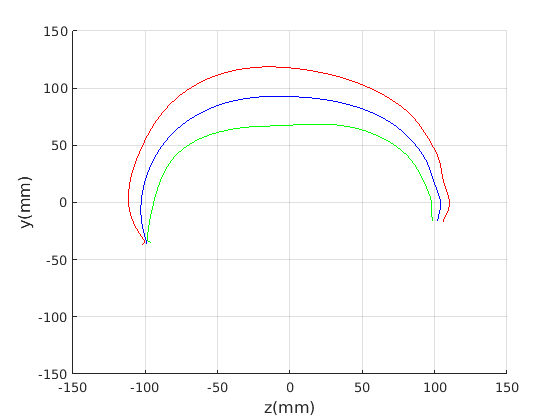

8 A case study of cranial profile model use for intervention outcome evaluation

In this section we take a sample of 25 boys, who are craniofacial craniosynostosis patients, 14 of which have undergone one type of corrective procedure (BS) and the other 11, another corrective procedure (TCR). Providing that the heads are sufficiently symmetrical and are amenable to ellipse fitting, we can parameterise all of these patients’ heads using our scale-normalised craniofacial profile model (2D model with face cropped out). We can then plot their pre-operative and post-operative parametrisations and compare them with the parameterisations of the 100 training examples. The expected result is that the parameterisations should show the head shapes moving nearer to the mean of the training examples. It also reveals which of the dominant modes of shape variation are most affected. The results are shown in figures 31 and 32.

For the BS patient set, the Mahalanobis distance of the mean pre-op parameters (red triangle in Fig. 31) is 4.670, and for the mean post-op parameters (blue triangle) is 2.302. For shape parameter 2 only these figures are 4.400 and 2.156.

For the TCR patient set, the Mahalanobis distance of the mean pre-op parameters (red triangle in Fig. 32) is 4.647, and for the mean post-op parameters (blue triangle) is 2.439. For shape parameter 2 only these figures are 4.354 and 2.439. We note that most of this change occurs in parameter 2, which corresponds to moving height in the cranium from the frontal part of the profile to the rear. In these figures we excluded one patient, who preoperatively already had a near-mean head shape (see red cross near to the origin in Fig. 32, so any operation is unlikely to improve on this (but intervention is required in order to relieve potentially damaging inter-cranial pressure).

It is not possible to make definitive statements relating to one method of intervention compared to another with these relatively small numbers of patients. However, the cranial profile model does show that both procedures on average, lead to a movement of head shape towards the mean of the training population. An example of analysis of intervention outcome for a BS patient is given in Fig. 33 and a TCR patient is given in Fig. 34. The particular example used is highlighted with circles on figures 31 and 32 to indicate pre-op and post-op parametrisations. To our knowledge this is the first use of statistical 3D craniofacial shape models in a clinical study.